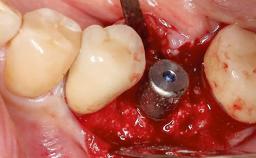

Surgical Management of Peri-Implantitis: Removal of Implant Due to Recurrent Infection Using an Implant-Retrieval Tool

Despite anti-infective surgical treatment, some patients may experience recurrent infection and progressive bone loss requiring additional treatment. This case describes a conservative approach using an implant retrieval tool without the need for excessive bone removal or use of a trephine.